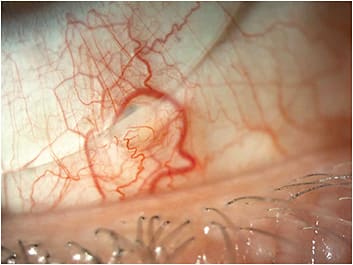

While being seen in the office, a 1.5mm hypertrophic conjunctival nodule with sectoral inflammation and injection on the bulbar conjunctiva was seen. Measurements and slit lamp photographs were taken. Measurements of the apex in relation to the edge of the lens, as well as the width, and an estimation of the height were noted. All other ocular findings were unchanged since his last visit. The decision to modify the lens incorporating toric haptics and a microvault were made (Figure 1).